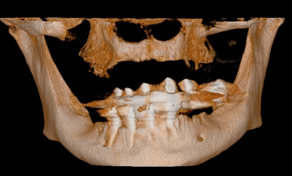

Paciente com edentulismo total maxilar foi indicado pelo profissional protesista para a instalação de implantes na região dos elementos ausentes: 11, 21, 22, 34, 35, 36, 45 e 36. Após exame clínico inicial e complementar com radiografia panorâmica e tomografia computadorizada de feixe cônico (TCFC), notou-se severa reabsorção óssea na maxila. No caso apresentado, a técnica de levantamento de seio maxilar não estava indicada, dado as características anatômicas dos seios maxilares hipoplásicos associadas à extensa reabsorção óssea de rebordo alveolar (Figuras 1 e 2).